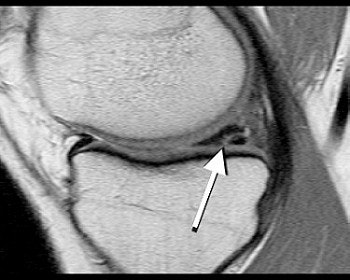

| The most common type of meniscal tear -- the horizontal or oblique partial-thickness tear -- is shown above (arrow). This type of lesion had a very similar prevalence on the asymptomatic contralateral side. |

Type A tears were found medially and laterally in 32 symptomatic knees and in 29 asymptomatic knees. Type B and C tears were seen medially and laterally in 18 symptomatic knees and in 5 asymptomatic knees.